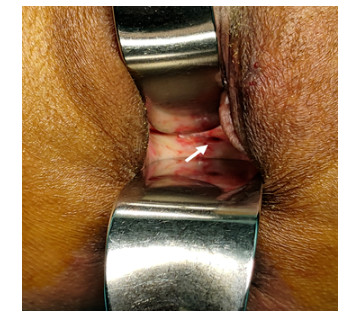

妇科检査:

外阴:萎缩;阴道:前后壁明显纤维化,暴露较困难,质硬,阴道窥具无法完全打开,阴道长度约3cm,顶端封闭;阴道顶端稍偏左侧可见大小约0.5cm瘘口,可见有清亮尿液溢出;肛查:直肠粘膜光滑,子宫前位,宫体萎缩,质中,无压痛;双附件:未扪及明显异常。

手术方式:

放疗后膀胱阴道瘘修补+Martius组织瓣移植术+全阴道封闭术。